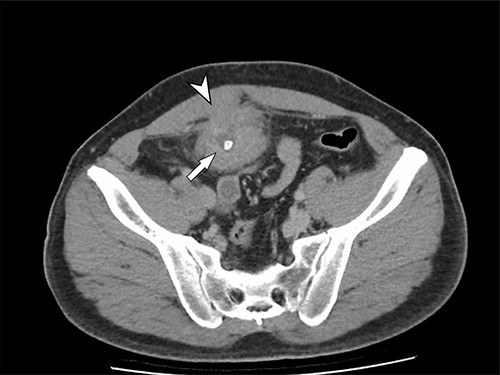

The patient had an uneventful recovery post operation. A retrospective review of the patient’s previous imaging revealed evidence of an appendicolith at the time of appendicitis diagnosis (Fig. 4). Despite the presence of the appendicolith on the preoperative CT, the histology of the resected appendix did not describe the presence of the imaged appendicolith. In addition, there was no evidence of a urachal lesion then on the initial imaging (Fig. 5), nor was there an intraoperative report of abdominal abnormalities during the appendicectomy. Therefore, it is hypothesized that the urachal lesion was an abscess secondary to the retained appendicolith from the appendicectomy.

Axial CT image. Arrow indicates appendicolith present within the appendix, with minor fat stranding surrounding the appendix.